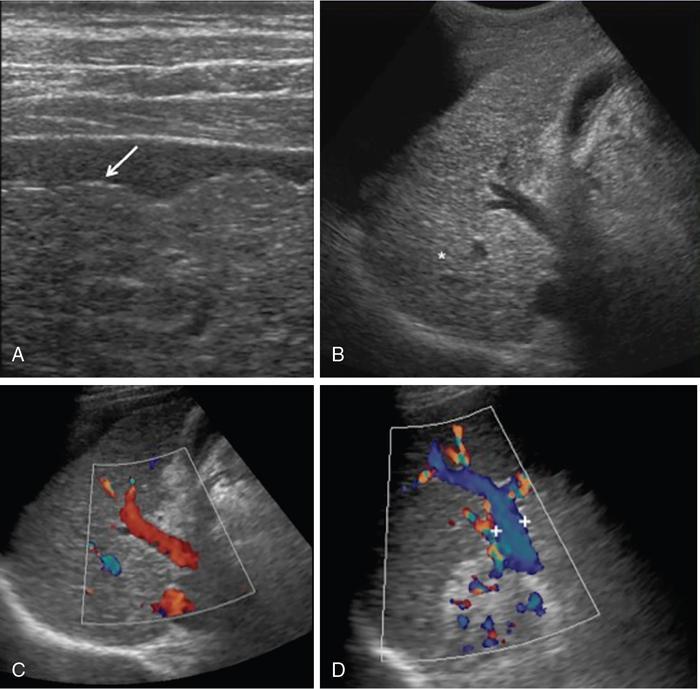

DIFFUSE PARENCHYMAL DISEASES OF THE LIVER Ishan Kumar, Ashish Verma The hepatic parenchyma is the site for multiple essential, interrelated, and complex metabolic activities to assimilate nutrients, detoxify the body, and synthesize vital molecules such as enzymes, hormones, cofactors and essential components of the coagulation pathway. The chemical reactions involved in each of these activities pose a threat to the hepatocytes, which may be damaged leading to the initiation of reparative processes. Further, the liver, being a highly vascular organ with multiple metabolic activities, is liable to be involved in many systemic vascular and metabolic disorders. On one hand, such changes cause healing of the tissue injury, but on the other hand, lead to diffuse parenchymal changes, which may result in suboptimal functioning of the organ. Such a condition is labelled as ‘diffuse liver disease’ and includes (a) diseases caused due to storage of certain chemical products of such chemical reactions labelled as ‘storage disorders’, (b) diseases caused due to reduction of blood flow to the organ, (c) parenchymal injury due to stasis of bile at various levels in the pathway due to varied causes, and (d) involvement of liver in systemic or organ-based inflammatory disorders. The mainstay of diagnosis of diffuse liver diseases is the detection of alterations in the biochemical parameters in blood indicative of liver function, which however is nonspecific to various aetiologies. The diffuse liver diseases in children are quite different from those in the adult population and constitute mainly of congenital or inherited metabolic and vascular diseases as opposed to diseases of acquired aetiologies in the latter population. The gross and microscopic pathological changes are accordingly different in the paediatric population and may be utilized to add specificity to the biochemical indicators as far as aetiological diagnosis is concerned. The invasive and potentially hazardous sampling mandated for histological evaluation of liver parenchyma has been replaced by an array of imaging modalities in recent times. The present chapter presents a review of the currently available imaging modalities (viz. cross-sectional imaging modalities such as ultrasonography, computed tomography [CT] and magnetic resonance [MR] imaging) for evaluation of diffuse liver diseases along with the pertinent imaging features and guidelines for their rational use in various indications. Also a short review of certain key technical and technological details is included. Jaundice and hepatomegaly are the most common clinical manifestations of liver disease. Anorexia is a nonspecific sign, often present in acute or chronic liver disease. Jaundice is a sign of increased bilirubin content in the blood, that can exist in four forms: (i) unconjugated bilirubin bound to albumin, (ii) unbound unconjugated bilirubin, (iii) conjugated bilirubin and (iv) δ fraction. Direct fraction includes both conjugated bilirubin and δ bilirubin. Conjugated hyperbilirubinemia is due to decreased excretion by liver or biliary tract obstruction. Pruritus, spider angioma on face and neck, ascites, portal hypertension, botchy palmer erythema, subcutaneous xanthoma, gastrointestinal (GI) variceal bleed, encephalopathy, renal dysfunction and pulmonary involvement are manifestations of advanced cirrhosis. Evaluation of total serum bilirubin and its fractional analysis into indirect (unconjugated) and direct (conjugated and δ fraction) bilirubin helps to distinguish between elevation caused by haemolysis and that due to hepatic dysfunction or biliary obstruction. Elevations in alkaline phosphatase (ALP), 5′ nucleotidase, and γ-glutamyl transpeptidase (GGT) levels are an indicator of biliary obstruction. However, it should be noted that normal growing children have significant elevations of serum ALP activity. AST (aspartate aminotransferase) and ALT (alanine aminotransferase) are significantly raised in acute hepatitis. ALT rise disproportionate to AST rise is seen in viral hepatitis. A predominant rise in AST is seen in echovirus infection, various metabolic diseases or alcohol-induced hepatitis. These aminotransferases are also elevated in NAFLD/NASH. ALT/AST rise is less marked in chronic liver disease. PT-INR, serum albumin levels can evaluate the hepatic synthesis function. Hypoalbuminemia suggests a bad prognosis. γ-Globulin is elevated in autoimmune hepatitis (AIH). Alpha-fetoprotein is raised in hereditary tyrosinemia or hepatic neoplasms. Indications of liver biopsy in the paediatric age group include neonatal cholestasis, metabolic liver disease, NAFLD, congenital hepatic fibrosis, abnormal biochemical liver tests of unknown aetiology, intestinal failure associated liver disease, acute liver failure and liver tumours. Although biopsy of children and infants is considered a safe procedure, due to incidences of shock, the North American Society for Pediatric Gastroenterology and Nutrition (NASPGHAN) has recommended liver biopsy in children not to be necessarily performed as outpatient procedures. Sonography-guided percutaneous liver biopsy has been reported to be safer, more efficient, more comfortable and only marginally more expensive than blind biopsy. The use of coaxial technique, determination of the number of passes and use of track embolization were at the discretion of the interventional radiologists. In cases of uncorrected PT-INR elevation, transjugular liver biopsy can be performed. Ultrasound (US) is a valuable tool in the diagnosis and management of diffuse liver diseases. It provides useful information about the size, surface, parenchymal architecture, biliary channels and blood flow of the liver. US examination of the liver is performed in the supine position with a convex (5–7.5 MHz) probe. High-frequency (7.5–12 MHz) linear transducers can be used in young infants because of their small size. US examination can be completed with the colour Doppler technique and US elastography, if needed. CT protocol typically requires image acquisition during the multiple phases with a slice thickness of 5 mm or less and a pitch ranging from 1 to 1.5. Contrast injected is 2 mL/kg through manual or mechanical injection. The arterial phase begins at 10–15 seconds and the portal phase is at 20–40 seconds after contrast injection. Equilibrium phase is obtained at 3 minutes, when needed. MRI protocol to evaluate paediatric liver chiefly includes free-breathing sequences, due to the challenge offered by an inadequate breath-hold in these patients. Due to the same reason, motion insensitive single-shot HASTE sequences or motion insensitive T1-weighted spoiled GRE single-shot sequences are also widely utilized in paediatric MR examinations. In slightly older children with a relatively uniform breathing pattern, external trigger signals from a breathing belt, or navigator techniques may be used to overcome motion artefacts from breathing. T1- and T2-weighted turbo spin-echo (TSE) sequences and T2-weighted single-shot sequences in axial and coronal planes are initially acquired to evaluate the anatomy and screen for pathologies. This is followed by a gradient echo (GRE) images to examine vascular structures. Multiecho images with T1-weighting can be acquired to evaluate the fat content of lesions. Contrast-enhanced MRI with intravenous injection of gadolinium (Gd)-based contrast agent is performed as routine in cases with suspected portal hypertension or in any associated suspected neoplastic lesion. This is usually clubbed with MRA for vascular mapping. Arterial phase and portal phase should be acquired 10–15 seconds and 20–30 seconds, respectively after the start of contrast agent injection. GRE T1-weighted sequence should be repeated continuously four or five times to include achieve all phases of liver perfusion. Finally, steady-state imaging should be performed in the equilibrium phase (3 minutes) using T1-weighted and T1-weighted fat-suppressed imaging sequences. MRI contrast media should be administered with caution after evaluation of eGFR, and is safer than the iodinated contrast media needed for CT scan examination, and is hence preferred. Liver size measurement is commonly obtained in one of the two ways (a) an anterior to the posterior measurement of the liver in the midclavicular line, (b) a dome-to-tip longitudinal measurement of the liver in the midclavicular line. Table 9.8.1.1 provides suggested upper limit values of liver and spleen length for various paediatric age groups. Despite advances in 3D US, volume measurements of liver size have not been incorporated in the routine clinical practice because it is time-consuming, requires considerable skill and technically difficult fusion of multiple 3D sweeps. Nonalcoholic fatty liver disease (NAFLD) is referred to as triglyceride accumulation in hepatocytes and encompasses a broad range of clinicopathological entities ranging from simple steatosis, steatohepatitis to cirrhosis. Its worldwide reported prevalence is approximately 2.6%–10% in the general paediatric population and as high as 38% of obese children under the age of 19 years. In India, the reported prevalence is as high as up to 22% in the general paediatric population and up to 45% in obese and overweight children. Hepatic steatosis currently is the most common cause of chronic liver disease in paediatric patients. Table 9.8.1.2 highlights the causes of hepatic steatosis in paediatric age group. The pattern of injury is similar to alcoholic liver disease. Nonalcoholic steatohepatitis (NASH) constitutes a subset of NAFLD, ranging from simple steatosis to inflammation and fibrosis. NASH in children has two distinct histological subtypes. Type 1 NASH resembles adult subtype with macrovesicular steatosis, lobular inflammation, and ballooning degeneration and perisinusoidal fibrosis. Type 2 NASH shows steatosis with portal fibrosis and is present in younger children with increased severity of obesity. ALT can be normal in 20% of the patient with NAFLD and liver biopsy is the gold standard for diagnosis as well as a semiquantitative assessment of disease severity. In clinical practice, the diagnosis and monitoring of NAFLD largely rely on ultrasonography. Grade I fatty liver refers to diffusely hyperechoic parenchyma with a well-visualized diaphragm (Fig 9.8.1). Bright liver with loss of periportal echogenicity and indistinctly visualized vessels is referred to as grade II and blurring of the diaphragm is classified as grade III fatty liver. Limitations of the US are lack of objective quantification and diminished sensitivity in cases where biopsy-proven steatosis ratio is less than 30%. Moreover, hepatic fibrosis and inflammation in cases of NASH are sonographically indistinguishable from simple steatosis. Contrast-enhanced US can diagnose the presence of fibrosis in NAFLD, which is evident from the decreased accumulation of microbubbles in the liver parenchyma. The distinction between hepatic steatosis and fibrosis is important clinically, as fibrosis can progress to cirrhosis if left untreated. US elastography has emerged as a promising technique to screen the children with NAFLD to look for ongoing steatohepatitis/fibrosis. Transient elastography is the most popular elastography technique which has shown excellent accuracy in the adult population with chronic hepatitis. However, its accuracy in NAFLD is significantly lower and the data of effectiveness in the paediatric population is limited. Acoustic radiation force impulse imaging (ARFI) has been shown to have a good correlation with AST/ALT ratios in obese children with NAFLD. An ARFI elastography value of >1.19 m/s predicts NASH-related hepatic changes in these patients while a value >1.75 m/s is suggestive of cirrhosis. Another study on shear-wave elastography has shown a high correlation in paediatric NAFLD patients with biopsy-proven hepatic fibrosis. A value of >5.1 kPa strongly predicts the presence of fibrosis whereas a value of >6.7 kPa is suggestive of stage ≥F2 fibrosis (Brunt scoring system). CT is a common modality utilized for assessment of hepatic pathologies, however is seldom used for assessment of NAFLD because of the risk of ionizing radiation. On noncontrast CT, liver attenuation <40 HU or hepatic attenuation 10 HU lesser than that of the spleen is considered as a sign of steatosis. Recent literature advocates the utilization of MRI in the evaluation of NAFLD. Fat imparts high signal intensity to the liver parenchyma on T1-weighted spin-echo MR images while it is mildly hyper- to hypointense on T2-weighted images. Conventional spin-echo imaging is relatively insensitive to mild-to-moderate fatty infiltration of the liver. The most commonly employed technique for detection of steatosis is chemical shift imaging (Dixon technique or dual-echo method) which utilizes two sets of gradient-echo images of the liver, that is in-phase and out-of-phase. On in-phase echo-time, water and fat signals add whereas, on out-of-phase echo-time, water and fat signals cancel each other. In nonfatty livers, the signal intensity of the liver parenchyma is unchanged between in- and opposed-phase images whereas a fatty liver shows a notable reduction of signal intensity on the opposed-phase images. Iron deposition in the liver can interfere with the assessment of steatosis. MR spectroscopy has been one of the most reliable techniques for the evaluation of hepatic steatosis (Fig 9.8.1.2). Protons in water molecules resonate at 4.7 ppm while that in triglyceride molecules resonate predominantly at 1.3 ppm. Other smaller lipid peaks can be obtained at 0.9, 2.0, 2.2 and 5.3 ppm. In a healthy nonfatty liver no triglyceride peak should be present. The presence of fat can allow measurement of area under water peak versus area under fat peaks to procure hepatic fat fraction. Proton density fat fraction (PDFF) measurement by MRI is another promising objective technique for quantification of steatosis in the paediatric patient. PDFF is the ratio of the density of mobile fat protons and the total density of protons including that from triglycerides and mobile water. Magnetic resonance elastography (MRE) is suggested as a noninvasive tool to evaluate liver stiffness that correlates with the degree of fibrosis. The technique is based on measuring the propagation of shear waves through liver parenchyma. A cut-off value for liver stiffness of 2.27 kPa has been suggested to predict Ludwig grade 2 or higher fibrosis. The technique depends on measuring the propagation of shear waves through the hepatic parenchymal fibrosis and differentiation of low-grade fibrosis from high-grade and also it may be feasible to distinguish steatosis from steatohepatitis. Success rate and accuracy of MRE is higher than US-based transient elastography. Cirrhosis is referred to as diffuse end-stage chronic liver disease characterized histologically by fibrosis and nodular regeneration, along with the disorganization of liver architecture. Although various underlying aetiology can lead to cirrhosis in children (Table 9.8.1.3), the most common causes in India are posthepatitic cirrhosis, Wilson’s disease (WD), AIH, biliary cirrhosis, biliary atresia and other metabolic diseases. In 5%–15% cases, the cause of cirrhosis may remain undetermined and is known as cryptogenic cirrhosis. Imaging is central to the diagnosis and management of children with cirrhosis (Fig 9.8.1.3). The role of imaging extends from diagnosis of cirrhosis to identification of complications and detection and characterization of nodules in cirrhotic liver. The imaging findings consist of changes in liver morphology, parenchyma and contour of the liver, vascular changes including portal hypertension, liver nodules and other complications of cirrhosis. Cirrhosis can lead to volume redistribution, which can be evaluated using either the US, CT, or MRI. Signs of early cirrhosis are atrophy of the segment IV, evident on imaging by increased fat segment IV and portal vein and between segment IV and left lobe. Signs of advanced cirrhosis are atrophy of the right lobe and segment IV with compensatory hypertrophy of left lobe and caudate lobe and fatty expansion of GB fossa. In some patients, a sharp notch is seen in the posterior surface of the liver (segment VI/VII). Some aetiology of cirrhosis may have different patterns of volume redistribution such as atrophy of left lobe and posterior segments in primary sclerosing cholangitis, diffuse hypertrophy in primary biliary cirrhosis, and absence of caudate hypertrophy in WD. The US can detect changes in liver segmental volumes based on linear measurements. C/RL (caudate/right lobe) ratio >0.65 calculated by comparing the transverse length of caudate and right lobe at the portal bifurcation, is a sign of cirrhosis. CT/MRI-based segmental volumetric analysis can reflect the morphological changes more effectively. Liver parenchyma in children appears as isoechoic to hypoechoic compared to the renal cortex in the US. The neonatal liver may reveal a bright echotexture. Hyperechoic parenchyma is seen in the fatty liver or liver fibrosis. Cirrhosis is seen as coarse and heterogeneous parenchyma. The liver surface in normal children appears as a hyperechoic, straight and regular line. The liver surface with diffuse irregularity or nodular surface is present in cirrhosis. CT and MRI in frank cirrhosis can reveal heterogeneous parenchyma along with the irregular surface. Diagnosis of early cirrhosis and fibrosis cannot be reliably made by the US where parenchyma may appear within normal limits. Similarly, CT and conventional MR sequences are also insensitive in early cirrhosis although early fibrosis can be seen as T1 hypointense/T2 hyperintense areas on MR and may show subtle enhancement. These T2 hyperintensities can be present as perilobular bands, perivascular cuffing, bands surrounding regenerative nodules, patchy fibrotic areas, or diffuse reticulation (honeycomb pattern). The role of US elastography and MR elastography is increasing in paediatric liver diseases for the detection of fibrosis and early cirrhosis and has been discussed in the previous section. US examination should be complimented with Doppler of the portal vein and hepatic veins if US features are suspicious of cirrhotic or fibrotic changes. The diameter of the portal vein increases with age. The mean diameter of the portal vein is 3.5 mm in children <5 years, 6.3 mm in 6–12-year old children, and 7–11 mm in >12-year-old children. Portal vein diameter is increased in portal hypertension; however, no reliable age-dependent cut-off values exist for the PV diameter in the diagnosis of portal hypertension in paediatric patients. Peak portal vein velocity in the paediatric age group is usually above 20 cm/s in a nonfasting child (15 cm/s in term neonate) along with some respiratory undulation. Peak portal vein velocity <16 cm/s in the paediatric age group is suggestive of portal hypertension. In term neonates, the values are above 15 cm/s. An increase in pulsatility of the portal vein (PI < 0.5) suggests portal hypertension. Reversal of portal vein flow (hepatofugal flow), presence of periportal collaterals or portal cavernoma, umbilical vein recanalization and various other collaterals are other signs of portal hypertension. Hepatic veins should be evaluated to rule out Budd–Chiari syndrome. CT or MR portal venography can comprehensively assess the extent and anatomical location of portosystemic collateral vessels in children with liver cirrhosis. Four groups of collateral channels can be identified: (a) periportal collaterals and portal cavernoma, (b) collaterals draining into SVC, that is left gastric vein (coronary vein), short gastric vein, oesophageal and paraoesophageal collaterals, (c) collaterals draining into IVC such as paraumbilical vein and abdominal wall collaterals, splenorenal and gastrorenal collateral, (d) mesenteric, retroperitoneal and haemorrhoidal collaterals. Various nodules can be seen in the cirrhotic liver including regenerative nodules, dysplastic nodules and HCC. The US is not sensitive in identifying these nodules and high-frequency linear-array transducer can contribute to their detection. CT and preferably MR can be used to characterize these nodules. Table 9.8.1.4 summarizes the imaging findings of these nodules on CT and MRI. It should be noted that HCC is rare in young children although it has been reported in children younger than 5 years in progressive familial intrahepatic cholestasis (PFIC) and Byler disease, biliary atresia. Recognizing the need for paediatric-specific guidelines for standardized interpretation and reporting CT and MR, ACR – LI-RADS (Liver Imaging Reporting and Data System) committee has convened the Pediatric LI-RADS Working Group in 2017. Hepatorenal fibrocystic diseases (HRFCDs) are developmental abnormalities of the liver and portobiliary system with associated fibrocystic degeneration of the kidneys. HRFCDs belong to the larger group of disorders collectively referred to as ‘ciliopathies’ a term describing the group of disorders affecting primary cilia which are an organelle present within the cholangiocytes. The ciliopathies in the liver is manifested as ductal plate malformation. Ductal plate is the embryonic precursor of the intrahepatic bile ducts and their abnormal development leads to cyst formation and alteration in portal venous development. Two major disorders are included in these malformations: (i) congenital hepatic fibrosis (affecting small intrahepatic ducts) and (ii) Caroli’s disease (affecting larger ducts). A combination of the CHF and CD is known as Caroli’s syndrome. Liver function test results in DPM may remain normal or be only modestly elevated. Few of congenital cystic liver pathologies are not associated with ciliopathies, such as autosomal-dominant polycystic liver disease (ADPLD) and portal fibrosis associated with congenital disorder of glycosylation (CDG) type Ib. Tables 9.8.1.5 and 9.8.1.6 innumerate the renal diseases and syndromes associated with ciliopathies. Carbohydrate-deficient glycoprotein syndrome type 1b Renal–hepatic–pancreatic dysplasia Oral–facial–digital syndrome type I US is the first-line modality, which can detect the distinctive morphological features of CHF that includes left lobe (segments II and III) hypertrophy, normal or hypertrophies segment IV, and atrophied right lobe. Preservation of the volume of the left medial segment is a feature that distinguishes CHF from cirrhosis resulting from viral hepatitis. The US can also detect changes in parenchymal echotexture, presence of splenomegaly, and can identify the evidence of cystic disease in the kidneys. Portal hypertension is one of the common presenting features of CHF despite normal hepatic lobular architecture and normal hepatic function. Application of the Doppler technique can detect the features of portal hypertension and cavernomatous transformation of the portal vein which can be present in up to 50% of the cases of DPM. The portal vein shows abnormalities in its ramification pattern with numerous, hypoplastic branches which are closely spaced, referred to as ‘pollard willow’ pattern. Studies have also shown enlarged hepatic artery and regenerative nodules in the arterialized hepatic parenchyma. In cases of Caroli’s syndrome, the US can easily identify cystic lesions or dilated intrahepatic bile ducts and can detect the stones in the ducts. Intraductal bridging (echogenic septa) can be seen traversing the dilated biliary duct lumen. Occasionally, the US can identify small portal venous branches surrounded by dilated biliary duct. Because of the absence of risks of ionizing radiation, US is the modality of choice in these children for long-term follow-up. CT can comprehensively demonstrate the morphological changes of CHF. Segmental computer-aided volumetric analysis of the hepatic parenchyma can identify the volume distribution with higher accuracy compared to the US. CT can also detect the parenchymal changes with higher sensitivity than the US. CT in these patients shows heterogeneously enhancing liver parenchyma, volume changes, and complete vascular mapping of the abdomen in cases of portal hypertension, identifying the portosystemic collaterals. Periportal cuffing can be identified on CT, indicative of periportal fibrosis. In Caroli’s disease, CT shows segmental and noncontinuous, saccular or fusiform dilatation of intrahepatic biliary radicals with the central enhancing dot representing portal vein branches (Fig 9.8.1.4). CT can identify the communication of the cyst with IHBD, differentiating them from PCLD. CT can also better detect the complications of CD such as cholangitis abscesses and cholangiocarcinoma. Seven per cent of the patients of CD can develop cholangiocarcinoma. MRI and MRCP seem to be a sensitive method for revealing biliary and renal abnormalities associated with congenital hepatic fibrosis and CD, even when sonography findings are normal (Fig 9.8.1.5). The parenchymal changes and heterogeneous architecture along with periportal fibrosis can be demonstrated on T2-weighted images, revealing hyperintensity along the portal vein and its branches. Regenerative nodules can be identified on T2-weighted and contrast-enhanced MRI. MRCP can delineate the communication between the cystic lesions and the biliary tree in cases of CD. Contrast-enhanced MRI can aid in the detection of complicating malignancies which can have a wide range of radiological appearances such as focal hepatic mass, intraductal mass, or biliary stricture. Multiplanar capability of MRI can enable its utility for preoperative planning in the affected children obviating the need for invasive preoperative cholangiogram to demonstrate the anatomy of the biliary tree. The differential diagnosis of Caroli’s disease is ADPLD, Von Meyerberg complex, choledochal cyst, sclerosing cholangitis, recurrent pyogenic cholangitis and peribiliary cysts. PCLD is seen on imaging as more than 20 round and smooth cysts without any communication with the biliary tree. Biliary hamartoma (Von Meyerberg complex) are seen as multiple/unique round uniform small cysts measuring 1–3 mm located close to portal tracts. Recurrent pyogenic cholangitis presenting with intra- and extrahepatic biliary dilatation is the most difficult diagnosis to exclude on imaging, however, the presence of saccular dilatation favours the diagnosis of Caroli’s disease. It should be noted that up to 20% of the cases of Caroli’s disease may have associated extrahepatic bile duct dilatation mimicking choledochal cyst and Caroli’s disease may even coexist with choledochal cyst. The presence of diffuse fusiform dilatation of the extrahepatic duct with less than 3 cm diameter combined with the characteristic intrahepatic ductal findings may help differentiate patients with Caroli’s disease from patients with a choledochal cyst associated with intrahepatic biliary dilatation. Routinely 1–2 mg of iron is absorbed by the intestine in a healthy child. Iron is recycled by extravascular haemolysis in the liver to meet the required amount (25 mg) in the spleen and bone marrow through Kupffer cells. Excess iron is bound to ferritin and hemosiderin in the hepatocytes. Excess iron in the body may be deposited in the liver, spleen, lymph nodes, pancreas, kidneys, pituitary, myocardium and GI tract. Up to 10–20 mg of excess iron does not cause tissue damage, in which case the term haemosiderosis is applied. Functional and structural impairment of the tissues occurs if the iron load (50–60 g) exceeds the compensatory mechanisms. In these cases, the term hemochromatosis is applied. Primary hemochromatosis is a genetic disorder occurring through mutation in the HPE gene which causes increased absorption of iron through the intestine. The secondary nongenetic form is more common and is caused due to multiple blood transfusions (transfusional haemosiderosis) in haematological disorders such as myelodysplastic syndrome, aplastic anaemia, beta-thalassemia major (transfusion haemosiderosis). Prolonged and excessive iron deposition can lead to endocrine abnormality, cardiac failure and liver parenchymal disease. Liver biopsy was considered as a reference standard for the detection and quantification of iron overload in hepatic parenchyma. However, it is largely replaced by radiological techniques because of the invasive nature and small size of sampled tissue while doing a single-site biopsy. The US cannot detect the features of iron overload in the liver parenchyma; however, it can be useful in detecting the complications of iron overload such as cirrhosis, hepatocellular carcinoma (HCC) or features of portal hypertension. CT scan is also of limited utility in hemochromatosis. Attenuation of >65 HU (15–130) with low attenuation of hepatic vessels relative to liver parenchyma on noncontrast CT is suggestive of iron overload, however can also be seen in WD, glycogen storage disorder, long-term amiodarone administration. MRI is the primary radiological modality used for diagnosis of iron distribution, quantification and monitoring of treatment response in liver iron overload (Fig 9.8.1.6). Various MRI techniques have been devised for iron overload estimation. This technique compares the signal intensity of liver parenchyma with the signal intensity of paraspinal muscles, which are assumed to be unaffected by iron content. GRE sequences are obtained with TR of 120 ms, flip angle 200, and varying TE of 2, 4, 9, 14 and 20 ms. Three ROIs of 1–2 cm are drawn in liver parenchyma and one on each paraspinal muscles. Liver iron concentration can then be obtained using a free online calculator provided by the University of Renne. Images are obtained with TR 2500 ms, flip angle 900 and variable TE of 6, 9, 12, 15, 18 ms. The images can be used to draw automated ROI covering the right lobe of the liver (excluding vessels) in the largest area and a T2 map of the same images can be generated. The technique quantifies the T2 shortening due to proton exchange between bulk water and exchangeable protons in ferritin. T2* takes into account the contributions of the T2 (1/R2) effects and the microscopic inhomogeneities introduced in (B0) by the hemosiderin clusters. For T2* measurement single breath-hold multiecho GRE sequences with TR of 25 ms, flip angle of 20 degrees, TEs every 0.25 ms from 0.8 to 4.8 ms are obtained. R2 * (1/T2*) values can be generated with ROI drawn from a single midhepatic section by drawing an ROI following the boundaries of the liver and excluding hilar vessels. Liver iron concentration can be obtained using a formula: [Fe] = 0.202 + 0.0254 R2*. This technique detects the enhancement in the local magnetic field caused due to ferritin or hemosiderin using a 3D breath-hold multiecho GRE sequence with the use of chemical shift–encoded water/fat separation, T2*/R2* mapping, and B0 field mapping. A quantitative susceptibility map of the parenchyma is generated. A local relative susceptibility value (ΔB0) is obtained drawing ROI which is expressed in parts per million (ppm), related to local iron deposition. With the ongoing research, stress is being placed upon the multiparametric quantitative MR imaging protocol which includes MR elastography (for fibrosis), multiecho chemical shift–encoded GRE to measure proton-density fat fraction (for steatosis quantification) and R2* relaxometry (for iron overload estimation). Hepatic iron overload has been shown to predispose to the development of HCC in the younger age group. The detection of HCC in the setting of iron overload is less difficult on T2-weighted sequences because the presence of iron behaves like a nonspecific contrast medium, such as superparamagnetic iron oxide (SPIO). However, care should be taken while evaluating these lesions, which may appear like hepatic cyst or haemangioma. Any nodule detected in these patients should be evaluated and characterized by the use of intravenous gadolinium contrast. The liver processes various metabolic processes of the body and hence it can be affected by multiple inherited metabolic disorders. The affection of the liver in these disorders may be in the form of hepatomegaly, cholestasis, acute liver failure or hepatic encephalopathy. WD is an autosomal recessive disorder of copper metabolism, first described in 1912 by Samuel Kinnier Wilson. The primary defect is a genetic abnormality located at chromosome 13 and q14.3, coding for copper-transporting P-type ATPase. An average diet contains 3–5 mg copper, 40% of which is absorbed in the upper GI tract and which is almost completely excreted in bile. The genetic defect leads to abnormality in this excretory function that leads to copper accumulation in the liver and other organs and tissues including brain and cornea. Liver disease in WD can range from asymptomatic transaminasemia, acute or chronic hepatitis, fulminant hepatic failure, and cirrhosis. WD can be misdiagnosed as AIH because both can result in similar autoantibodies. Imaging findings of liver manifestations can be categorized into four groups: (i) morphological changes, (ii) parenchymal changes, (iii) perihepatic changes, (iii) other findings. On CT, copper deposition in the liver may present with increased attenuation of the hepatic parenchyma, however, associated hepatic steatosis can decrease the overall attenuation which is within normal limits in most of the patients. Contrast-enhanced CT can show hypodense as well as hyperdense nodules and surface irregularity. The disappearance of hyperdense nodules has been documented after penicillamine therapy. Various MRI features of liver disease in WD has been described in the literature that includes (a) T1 hyperintense/T2 hypointense nodules (2 mm to 1 cm), (b) T1 hypointense nodules, (c) multiple hyperintense septae leading to ‘honeycomb pattern’, (d) high-intensity septa, (e) absence of parenchymal changes on MR. 31P MR spectroscopy of the liver in WD can show elevated phosphomonoester (PME) resonance and reduced phosphodiester (PDE) resonance, which have been shown to normalize after penicillamine and vitamin K therapy. Gaucher disease (GD) results from a deficiency of lysosomal enzyme β-glucocerebrosidase leading to the accumulation of ‘Gaucher cells’ in various organs. Imaging can help in the detection and characterization of liver infiltration, hepatomegaly, fibrosis, cirrhosis, iron deposition and HCC, all of which are associated with GD. On imaging, hepatosplenomegaly is the hallmark of GD (Fig 9.8.1.7). Recent literature recommends the utilization of CT or MRI over the US for volumetric assessment of liver and spleen sizes in GD with the expression of liver volume as multiples of normal volume (MN). Weight-based formula is used for calculation of liver and spleen volumes: normal liver volume (mL) = 25 × weight (in kg) ; and normal spleen volume (mL) = 2 × weight (in kg). A target liver volume of 1–1.5 MN and a spleen volume of 2–8 is aimed by the therapeutic regimens. On MRI, low ADC of liver and spleen indicates greater infiltration and worse prognosis, with ADC values correlating with chitotriosidase levels. Fibrosis can be detected and quantified using US shear-wave elastography, MR elastography, and nonimaging–based transient elastography. Studies have indicated the presence of liver iron deposition in GD due to associated hyperferritinemia, which can be quantified using R2* relaxometry. Hepatic nodules can be identified on imaging on GD. Most commonly these nodules represent a focal accumulation of Gaucher cells and are known as ‘Gaucheroma’. These lesions are hyperechoic on the US, hypoattenuating on CT, T1 hypointense/T2 heterogeneous nodules on MRI. These lesions do not merit biopsy; however, care should be taken to identify the lesions suspicious for HCC, that is large, irregular, hypoechoic, hypervascular lesions, which mandate further evaluation by multiphasic contrast CT or MRI. Besides the liver, evaluation of abdominal imaging should attempt to detect changes in spleen and visualized bones. GD in the spleen can manifest with splenomegaly, fibrosis, nodules, subcapsular infarcts and splenic necrosis. Osseous features of GD are osteopenia, osteonecrosis, pathological vertebral fractures and Erlenmeyer flask deformity. These are a group of disorders caused by defects in metabolism or storage of glycogen which broadly present with hepatic, myopathic, cardiac or other manifestations. GSD type I (Von Girke disease) presents with hepatic involvement. The US in these patients shows hyperechoic liver parenchyma because of fatty replacement and glycogen deposition. CT shows variable attenuation because hepatic attenuation is increased by glycogen and decreased by steatosis. There is a well-known association with GSD and hepatic tumours such as adenoma, focal nodular hyperplasia and HCC (rare). Adenomas are the most common tumours in GSD which show variable echogenicity. These lesions may contain fat, haemorrhage, or rarely dystrophic calcifications. A fat component can be detected using chemical shift MRI. These lesions should be monitored serially and malignancy should be suspected in case of rapid growth. α1-Antitrypsin deficiency is a rare autosomal recessive disorder that can cause chronic severe paediatric liver disease. In infants, this disorder can have a presentation similar to biliary atresia or idiopathic neonatal hepatitis. Moreover, scintigraphy cannot distinguish between biliary atresia, because similar to atresia, it can show uptake by hepatocytes and absence of biliary excretion due to paucity of lobular biliary ducts. The US in the neonatal period can help distinguish between the two, as it shows normal gallbladder and hepatic parenchyma. Older children may show imaging evidence of hepatic fibrosis or cirrhosis. MR elastography in this disorder is accurate for identifying fibrosis with a cut-off value of >3 kPa predictive of fibrosis. Various systemic illnesses can present with liver disease. The table summarizes the hepatic manifestations of various systemic liver diseases. TABLE 9.8.1.7 Paediatric diffuse liver diseases though forming a small subset of overall morbidity in children pose a formidable challenge for diagnosis as most cases present at a relatively early age. Imaging in these cases aims to make an aetiological diagnosis and rule out any associated complications, as the initial diagnosis is usually established by the biochemical analysis of liver function. Screening sonography usually forms the initial screening modality with MRI being the next stop problem-solving modality. CT scan has taken a back seat in current practice due to radiation exposure and the need to inject iodinated contrast media, both of which can be obviated by MRI. The former modality however remains essential in case an interventional procedure to treat portal hypertension is contemplated or percutaneous sampling from areas difficult to access by sonography is to be done. With the availability of an array of imaging modalities, it remains essential for an imaging expert to be clear as far as the choice of modality and order of its usage during the course on management is involved so that the most optimum imaging protocol can be offered to the patient. PEDIATRIC BENIGN HEPATIC MASSES (INCLUDING INFECTIONS) Kushaljit Singh Sodhi, Anmol Bhatia, Akshay Kumar Saxena Liver neoplasms constitute around 2% of all neoplasms seen in the pediatric population, and around 6% of the total abdominal neoplasms. Only one-third of the liver tumours in children are benign, while two-thirds are malignant. Benign hepatic tumours in children include lesions which are specific to children like mesenchymal hamartomas and vascular tumours, and the lesions that are also seen in adult population, such as adenoma, focal nodular hyperplasia (FNH) and nodular regenerative hyperplasia (NRH). Further, benign hepatic lesions affecting children include a wide variety of infections of bacterial, fungal and parasitic origin. In the present chapter, we will be discussing about the benign hepatic tumours and hepatic infections commonly seen in the pediatric population. A wide variation has been reported in the use of terminology for the hepatic vascular malformations in literature. According to the standard nomenclature adopted by the International Society for the Study of Vascular Anomalies (ISSVA), liver vascular tumours in children are termed as liver hemangioma. Liver hemangiomas in children are classified as infantile and congenital. Infantile hemangiomas usually begin to grow after birth, continue to grow during the first year of life and enter an involuting phase between 1 and 7 years. These tumours are positive for glucose transporter-1 protein (Glut-1), a protein that facilitates the transport of glucose across erythrocyte cell membranes. On the other hand, congenital hemangiomas are fully developed at birth and are characterized by Glut-1 negativity. These are further subdivided into a rapidly involuting group and a noninvoluting group, with some overlap between these groups. Hemangioma is a model of the angiogenesis concept proposed by Folkman et al and its development is related to a combination of upregulation of factors that promote angiogenesis and downregulation of its inhibitors. Most of these tumours are diagnosed in the first year of life, with these being slightly more common in females. Most commonly, these present as an asymptomatic mass in abdomen; however, associated life-threatening presenting complications have also been reported. These include high-output cardiac failure as a result of large arteriovenous shunts or Kasabach–Merritt syndrome of coagulopathy, severe hypothyroidism and acute hemoperitoneum due to tumour rupture. Lesions can be focal, multifocal or diffuse. Multifocal lesions are usually small and homogenous in appearance, while larger lesions may show areas of hemorrhage, calcification, fibrosis and necrosis. The liver is grossly enlarged in diffuse disease, which may cause mass effect on surrounding organs and vessels. Multifocal lesions frequently are associated with multiple cutaneous infantile hemangiomas with a Glut-1 positive marker. Biopsy of these masses should be avoided as there is a risk of bleeding, and the diagnosis is made based on typical imaging features and involution at follow-up. Well-defined hypoechoic or hyperechoic lesion, which may show heterogenous echotexture because of central hemorrhage/necrosis. A variety of flow patterns may be seen on colour Doppler due to the presence of shunts which may be portosystemic, or arteriovenous shunts. The hepatic arteries and veins usually enlarged, with large feeding arteries and draining veins seen surrounding as well as within the lesions. The lesions are usually hypoattenuating to the liver parenchyma with speckled calcifications seen in up to 50% of cases. The enhancement pattern is similar to that of hemangioma in adults and shows intense peripheral nodular enhancement on arterial phase with progressive centripetal filling on venous and delayed phases. Small lesions usually show intense and uniform enhancement (Fig. 9.8.2.1). The lesions show hypointense signal on T1-weighted images (T1WI) and hyperintense signal on T2-weighted images (T2WI). The tumour shows internal vascular flow voids and centripetal enhancement (Fig. 9.8.2.2). Heterogeneous signal may be seen due to presence of hemorrhage, thrombosis and necrosis. Calcifications may be seen in about 16% of cases.